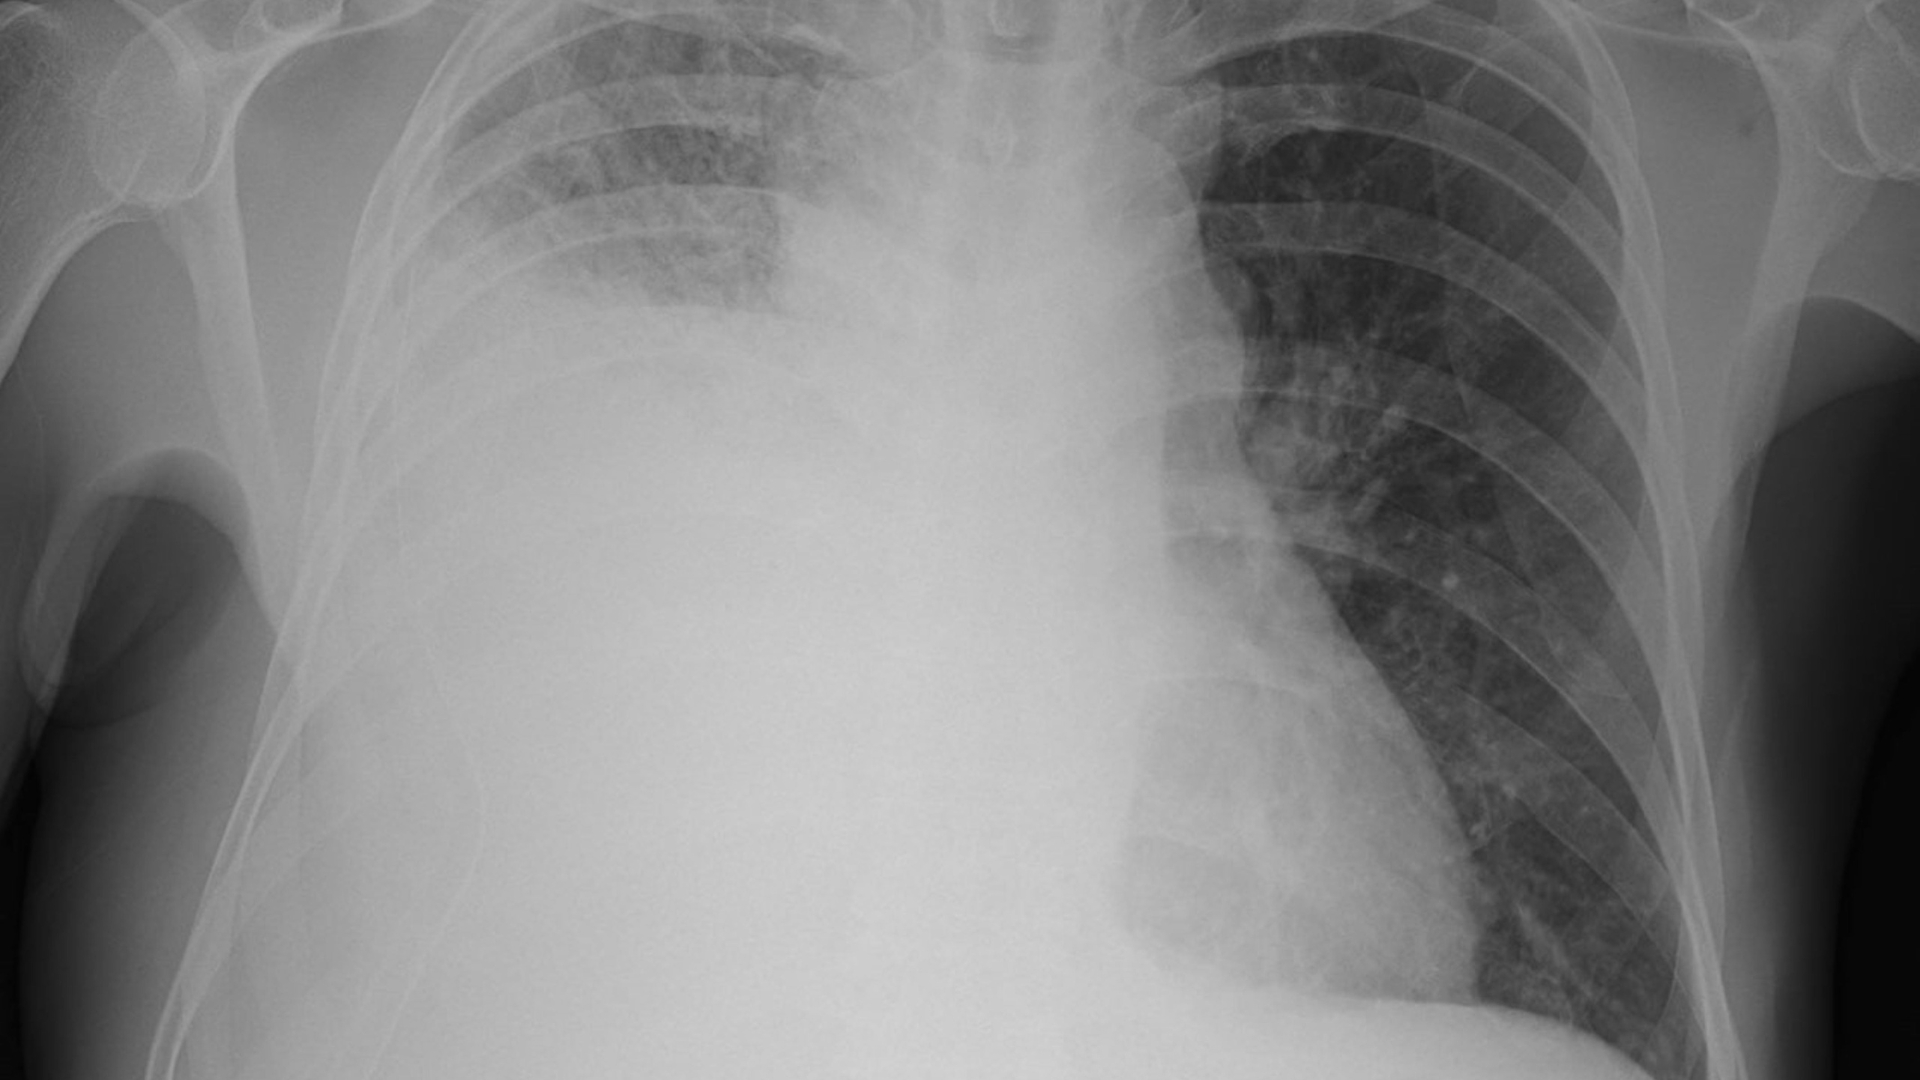

Âm thở giảm hoặc mất: Gợi ý giảm thông khí tại một vùng phổi, có thể do tràn dịch màng phổi, tràn khí màng phổi hoặc tắc nghẽn phế quản.

Tràn dịch màng phổi làm giảm hoặc mất âm thở ở vùng có dịch.

Tràn khí màng phổi gây mất âm hoàn toàn tại khu vực bị ảnh hưởng.

Xẹp phổi làm thay đổi sự phân bố âm thanh giữa các vùng phổi.